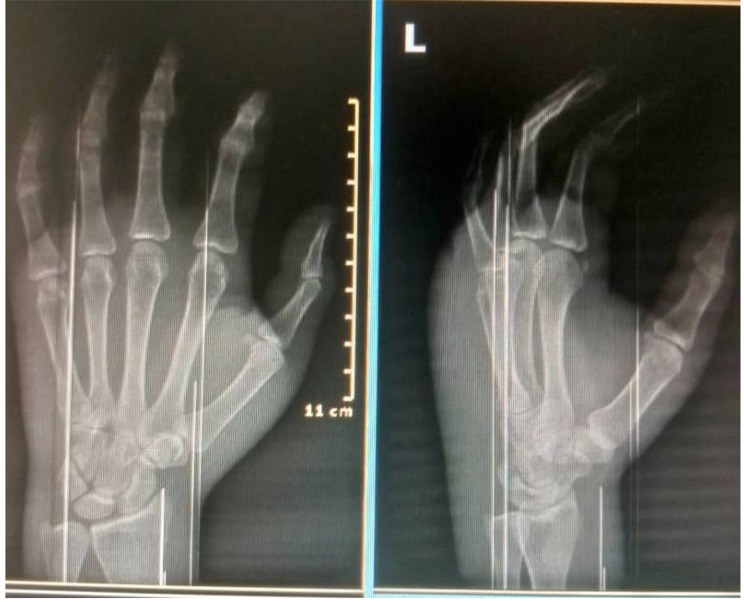

Laboratory investigations, including a complete blood count, C-reactive protein (CRP), and erythrocyte sedimentation rate (ESR), all fell within the normal range. Hand radiographs (Fig. 2) revealed significant soft tissue shadows and signs of osteopenia, without other identifiable pathologies. A CT angiogram (Fig. 3) yielded normal results, MRI (Fig. 4) showed edematous tissue in the hand and wrist. And Previously performed biopsyindicated normal tissue.

Fig. 2.

Xray image of the left hand